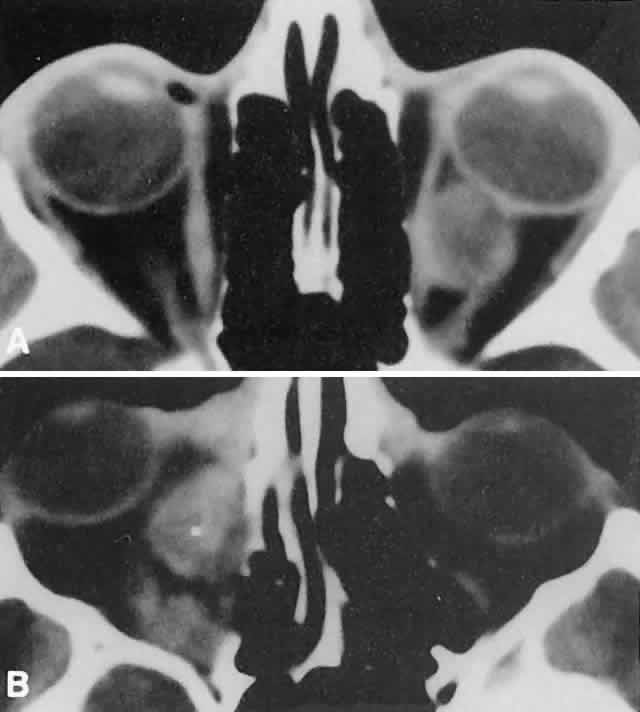

Within the orbit, rhabdomyosarcoma occurs most often, but not exclusively, in the superior nasal quadrant, with downward and outward displacement of the globe. CT scans show the topography of the orbital mass (Fig. 1A), as well as the possible extension into adjacent bone, paranasal sinuses, or the intracranial cavity. The circumscription that may be noted on CT is relative, because the lesion is not encapsulated and microscopically infiltrates normal tissue. Echography shows internal echoes of low-to-medium amplitude. Because the cellular tumor absorbs acoustic energy, the amplitude of the spikes falls off somewhat through the lesion (see Fig. 1B and C). MRI can help define the tumor's relationship to extraocular muscles (Fig. 2).

Fig. 1. A. Proptosis and downward, outward globe displacement developed over 2 days in a 3-year-old girl. A homogeneous mass fills the superomedial orbit. B. Contact B-scanning shows a relatively well-circumscribed mass with uniform internal echoes. C. Contact A-scanning shows the internal reflectivity to be of low to medium amplitude, consistent with a sarcomatous lesion. Biopsy results confirmed the diagnosis of rhabdomyosarcoma.

Orbital myositis may represent a greater proportion of cases of IIPT in childhood than in adulthood, and involvement of multiple extraocular muscles may occur more frequently in children than inadults. In orbital myositis, early diplopia and increased discomfort with attempted eye movement are typical symptoms. CT may show enlargement of one or more extraocular muscles in one or both orbits (Figs. 21 and 22). When a single muscle is involved, the specter of a primary or metastatic neoplasm within the muscle may be raised. However, external inflammatory signs, considerable pain and limited motility, and an explosive onset of symptoms within 24 hours all suggest orbital myositis. The uniform enlargement of the muscle, including its tendinous insertion (see Fig. 22), also helps distinguish the process from a neoplasm, which might be expected to produce a more focal, globular expansion. Echography may support the diagnosis of inflammation by showing edema in the episcleral space as a relative sonolucency between the scleral and orbital fat echoes (Fig. 23). Its CT counterpart is an increase in the radiodensity and thickness of the ocular tunica.

Fig. 21. A. This 16-year-old boy had acute onset of bilateral proptosis, pain, diplopia, chemosis, and conjunctival injection. B. Bilateral enlargement of the superior and medial rectus and inferior oblique muscles. Other sections showed similar involvement of other extraocular muscles.

Fig. 22. The uniform enlargement of the left medial rectus muscle, including its tendinous insertion, is characteristic of orbital myositis.

Fig. 23. Acoustic discontinuity between the globe and the orbital fat indicates inflammatory edema in Tenon's space.

In dacryoadenitis, external inflammatory signs are localized to the superotemporal quadrant, and CT shows enlargement of the lacrimal gland (Fig. 24). Lacrimal gland inflammation may be bacterial, viral, or a variant of IIPT. It is possible, however, that many cases of “idiopathic” dacryoadenitis represent unidentified viral infections. In bacterial dacryoadenitis, a leukocytosis with a left shift may be present.96 In questionable cases, a 1-week course of oral antibiotics can be administered to these patients. Among children, the probability that an enlarged lacrimal gland represents neoplasia rather than inflammation is lower than among adults, although epithelial lacrimal gland tumors occasionally may occur in the pediatric population and can produce external inflammatory signs. If the general signs and symptoms of IIPT are lacking, a biopsy should be performed.

Fig. 24. A. Nonbacterial dacryoadenitis may be unilateral or bilateral. External inflammatory signs are maximal in the superotemporal quadrant. B. The left lacrimal gland is enlarged, with a shape molded by the globe and orbital walls. A neoplasm usually can be ruled out by analysis of the history, CT findings, and echographic characteristics, but a biopsy may be required in equivocal cases.